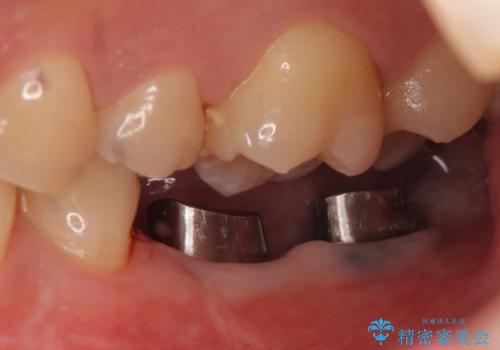

- 数年前に左下の奥歯を2本失ってから物が咬めないため何とかして欲しいと当院にいらっしゃった方の症例です。

左下にインプラント(ストローマン)を2本埋入し、オールセラミッククラウンによる補綴を行いました。